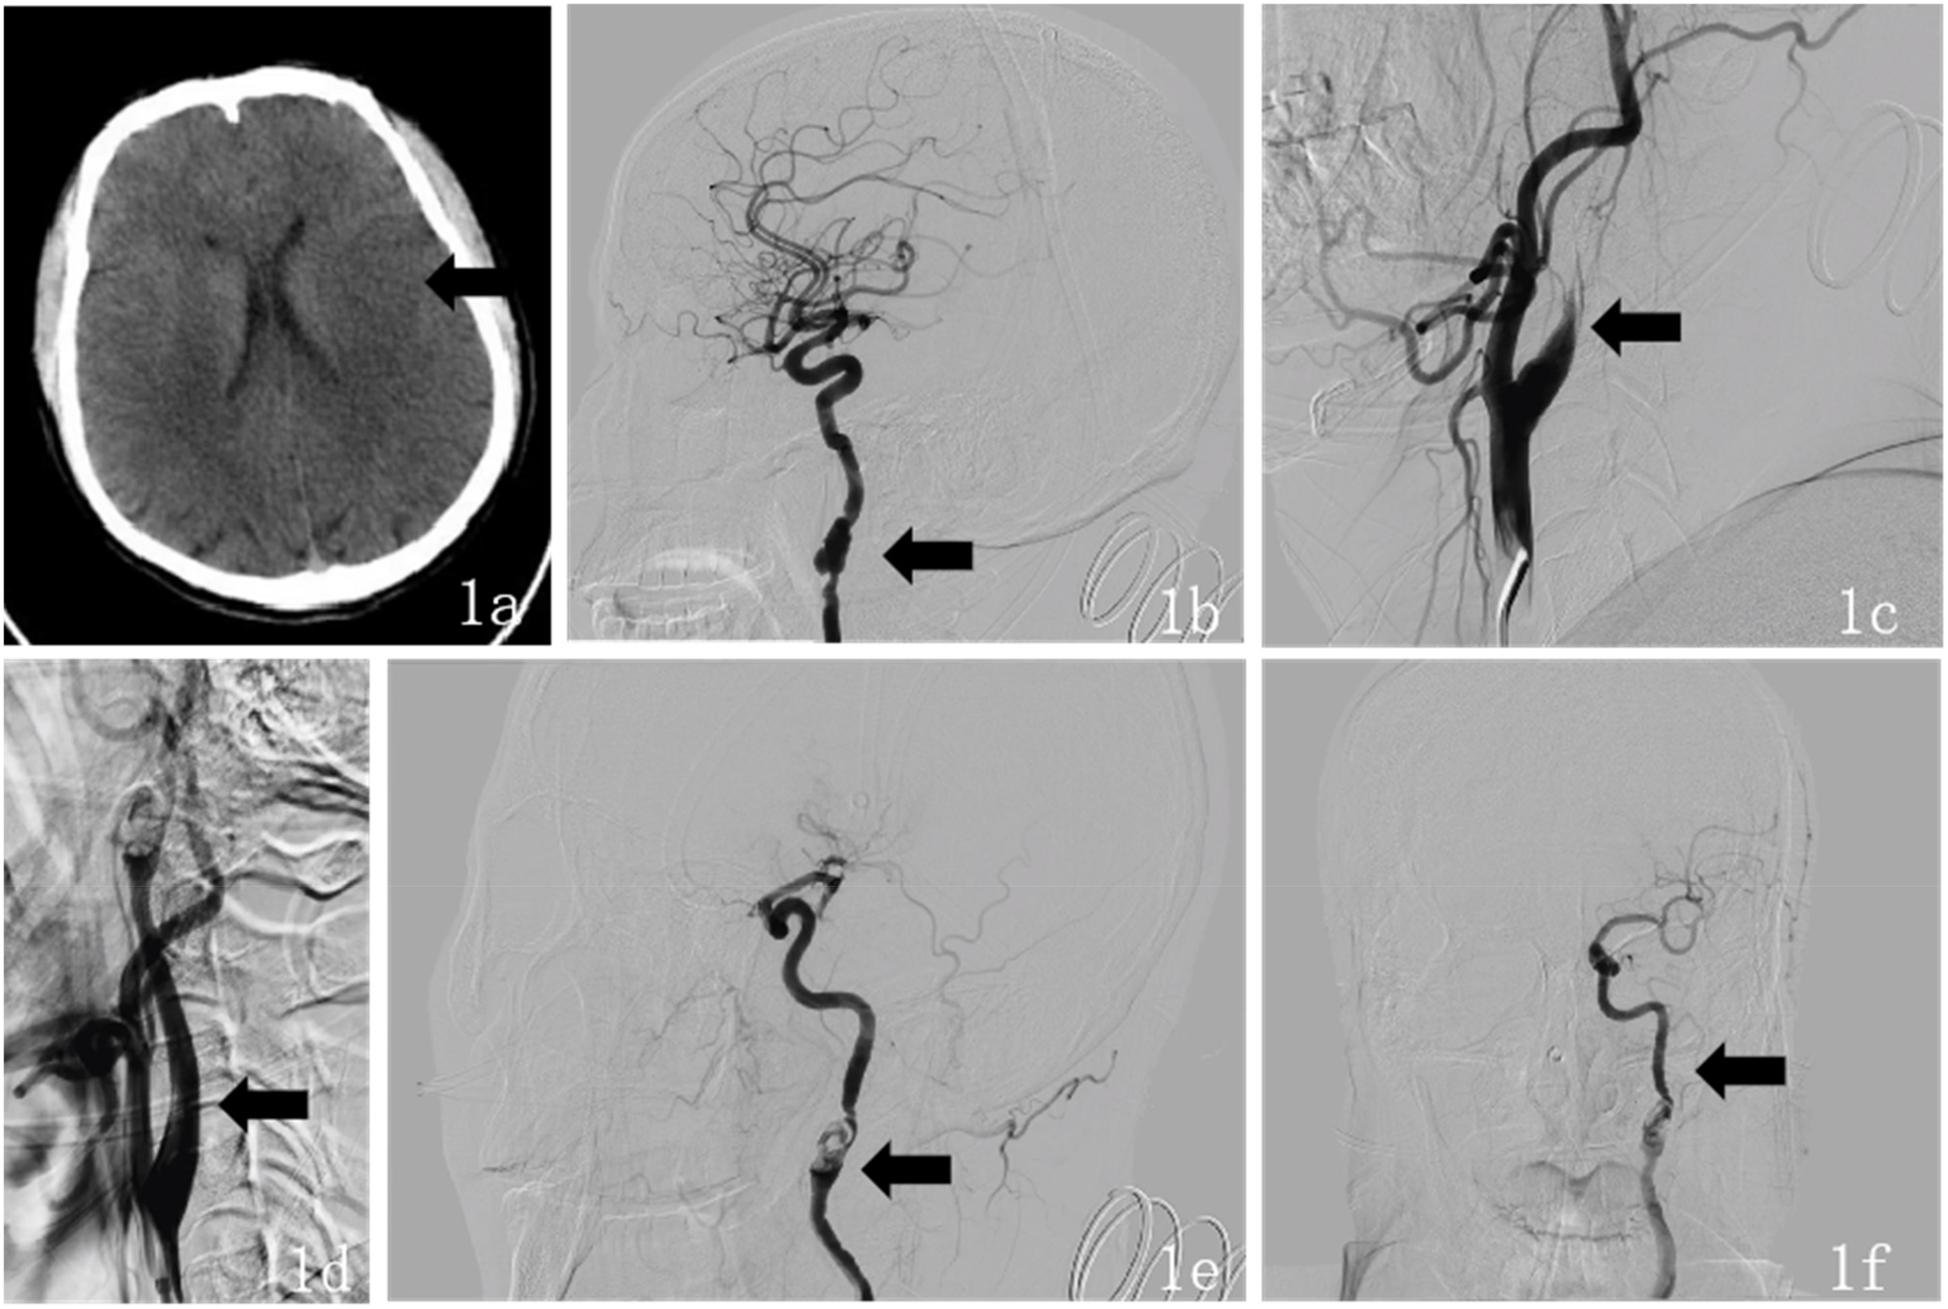

Postoperative neurological examination revealed no new neurological deficit signs. Follow-up cranial CT showed acute cerebral infarction in the left frontal, temporal, and parietal lobes, and a small amount of new hemorrhage in the infarcted margin (Figure 2a). The punctate hemorrhage at the infarct edge likely resulted from hemorrhagic transformation following reperfusion in the ischemic area post-acute stroke. This is associated with secondary hemorrhage caused by endovascular mechanical thrombectomy. After assessing the patient's hemorrhagic transformation and hemorrhage risk, the patient was administered oral enteric-coated aspirin 100 mg once daily, rosuvastatin calcium 10 mg once daily, 3-n-butylphthalide for improved circulation, urinary hallucinogens (a tissue kallikrein that improves hemodynamics and exerts neuroprotective effects by dilating blood vessels, promoting collateral circulation formation, and inducing angiogenesis) for neuroprotection, and supportive treatment. On the second postoperative day, the patient exhibited mixed aphasia, and muscle strength in the right limbs improved to grade 3. On the third postoperative day, routine follow-up MR brain scan, diffusion-weighted imaging, and MRA showed: (1) large-area acute/subacute cerebral infarction in the left frontal, parietal, and temporal lobes and left insular cortex; (2) a cavity infarction in the right temporal lobe; and (3) no significant abnormalities in brain MRA (Figures 2b,c). The right temporal lobe lacunar infarction was consistent with the first postoperative CT imaging and not a new infarction. On the fourth postoperative day, the patient's right-limb strength improved to grade 4, and he was able to walk with assistance. Though mixed aphasia persisted, it presented as non-fluent aphasia with severe deficits in auditory comprehension, naming, reading, and writing, but with relatively preserved repetition. Reexamination of head CT showed that the density of the infarcted area in the left frontotemporal and parietal lobes further decreased, and the amount of bleeding in the infarct margin area decreased. The patient was hospitalized for 8 days and discharged with clear consciousness, stable vital signs, and fair mental status. Upon discharge, the patient continued oral enteric-coated aspirin 100 mg once daily and rosuvastatin calcium 20 mg once daily. At the 1-month follow-up, DSA showed a patent left ICA and FMD in the C1 segment of both internal carotid arteries, consistent with prior angiography findings for FMD. At the 3-month outpatient follow-up, the patient was in good general condition with recovered speech function. After active rehabilitation exercises for limb mobility, he could walk unassisted and perform basic daily activities independently, which effectively alleviated the concerns of both the patient and his family. His mRS score was 1, muscle strength in the right limbs had improved to grade 4, and no new ischemic symptoms were observed. And Time line was shown in Table 1.

Figure 2

Three brain scan images labeled 2a, 2b, and 2c. Image 2a shows a CT scan with an arrow indicating a specific area. Image 2b is an MRI with an arrow pointing to another area. Image 2c is an angiogram displaying the brain's vascular structure.

Figure 2. (a) Postoperative (October 17, 2024) head CT findings: axial CT shows a large area of slightly low-density lesions in the left frontal, temporal, and parietal lobes, and a small area of slightly high-density lesions in the left basal ganglia. (b) Postoperative (October 20, 2024) MR head imaging, including plain scan, diffusion-weighted imaging (DWI): Axial DWI shows high signal intensity in the left temporal, parietal, and insular lobes. (c) Postoperative (October 20, 2024) magnetic resonance angiography (MRA) finding: MRA shows no significant stenosis or occlusion of the intracranial major arteries.